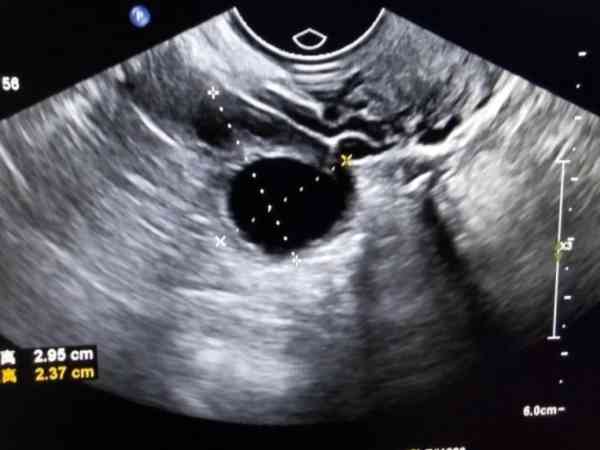

卵泡监测主要是看卵泡的发育过程以及是否有排卵,通过观察报告单上写的体内卵泡数量,以及卵泡的大小,可以判断出是否排卵,当报告单上卵泡数量减少,或者是成熟的大卵泡消失,只剩下未成熟的卵泡,就说明已经排卵了。

监测卵泡报告想要看卵泡多大了,可以观察报告单上的数字,比如说报告单上提示18*18mm,就说明有一个卵泡已经长到18mm了,此时卵泡已经发育成熟,有排卵的可能性,回去后安排同房即可。